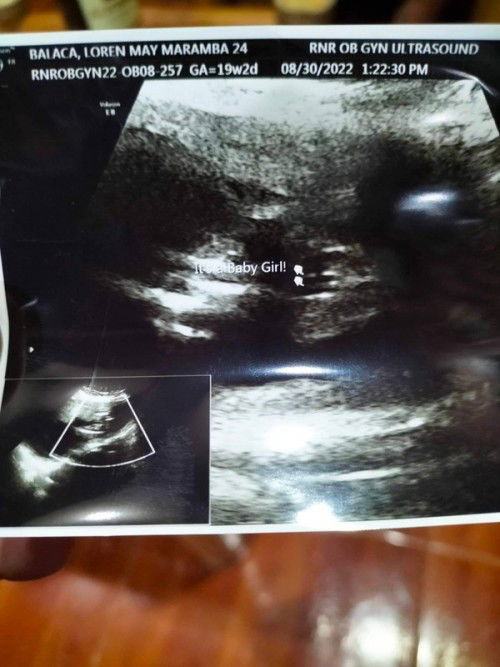

Same po burger din po sakin. 20 weeks and 2 days nung nakita gender nya 🥰

Yes sure na yan mi hehe, pag boy ganito makikita mo. 20wks din ako gehe

yes po sure nayan ganto po kase pag boy itlog agad makikita

Parang baby girl nga Momsh

burger, so possibly..

baby girl ata yan

Yes po. Burger po e